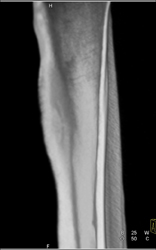

Osteoid Osteoma